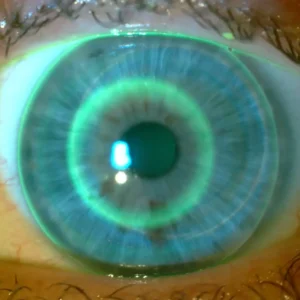

- umie ocenić dopasowanie soczewki na podstawie fluoresceiny i map topograficznych,

- Ocena fluoresceiny i map topograficznych